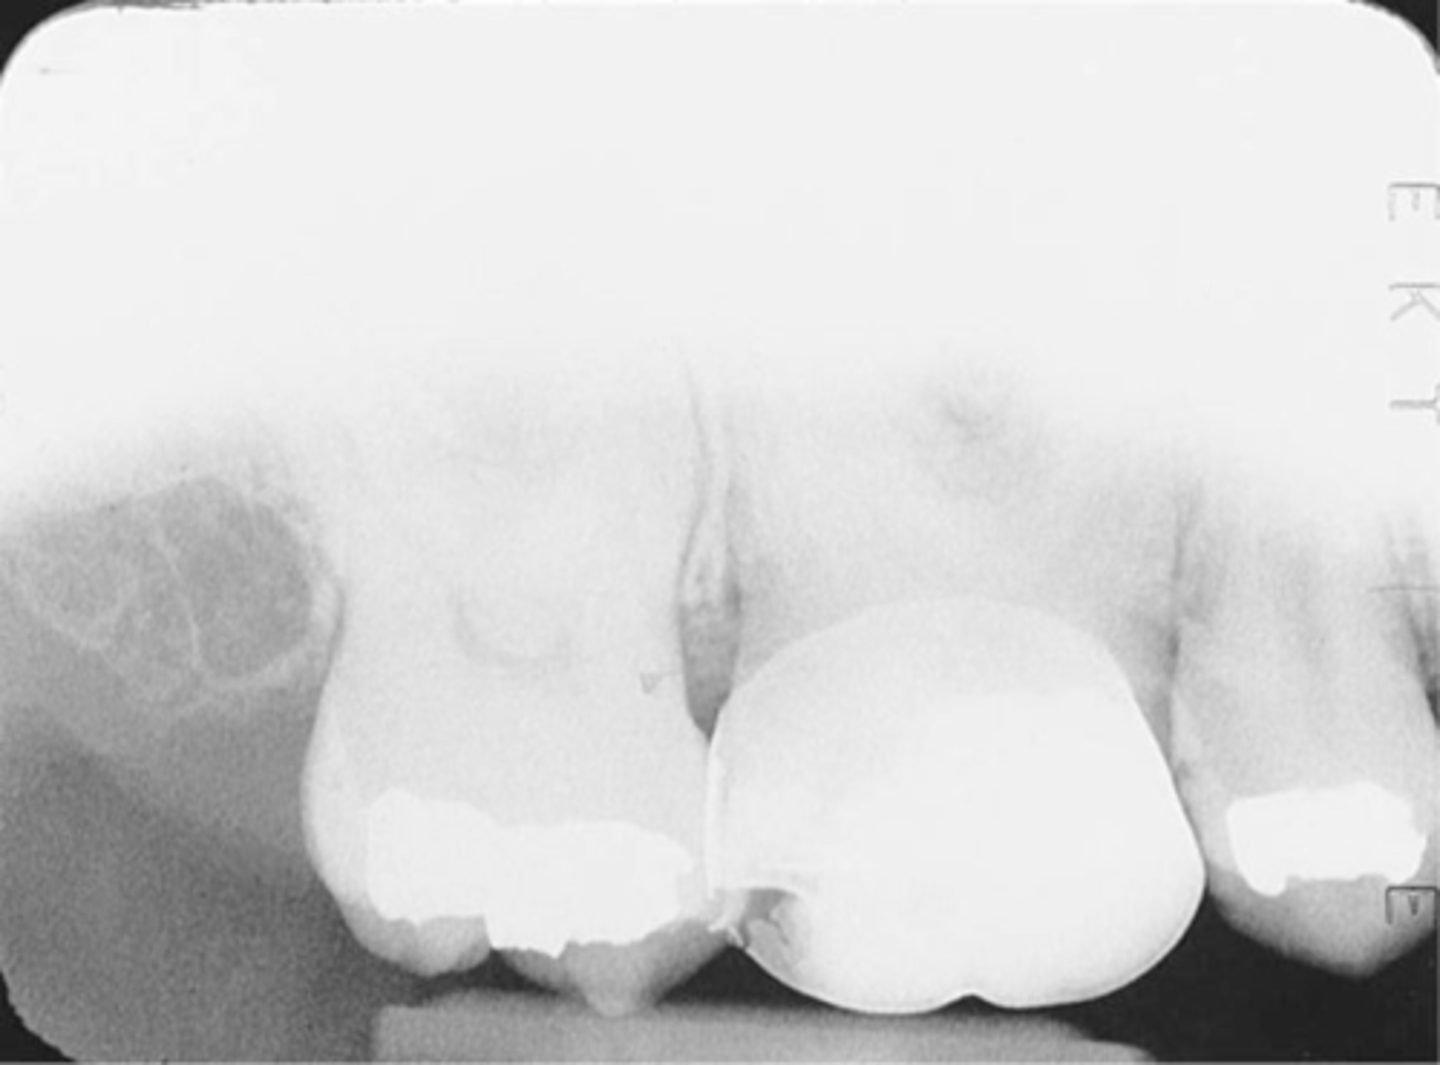

Premolar Bite-Wing

-Bite-Wing must be positioned so that the resulting image shows both max and mand premolars and the distal contact of the canines.

-Receptor must be positioned so that the front edge of the receptor is aligned with the midline of the mand. canine.

Incorrect Receptor Placement--Premolar Bite-Wing

-Distal surfaces of canines are not visible on the image

-Receptor was positioned too far posteriorly in the mouth; front edge of the receptor was not placed at the midline of the mand. canine.